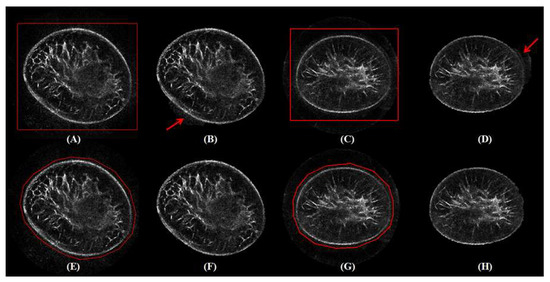

3.5. Robustness

3.6. Failure Case Analysis